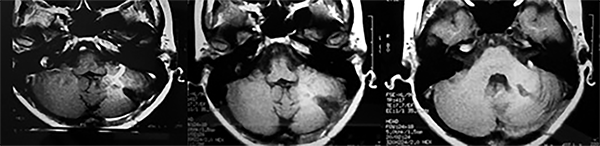

El estudio de RMN presenta una lesión bien circunscrita en hemisferio cerebeloso izquierdo con periferia de predominio hiperintenso en T1 y T2, y centro hipointenso, edema perilesional mínimo, así como una imagen de un vaso venoso alimentador que recorre hacia el ángulo pontocerebeloso izquierdo.

Lesión cerebelosa izquierda ponderaciones en T1 y T2, la flecha señala vaso nutricio hacia el ángulo pontocerebeloso izquierdo, se puede observar el centro de intensidad heterogénea con contenido quístico multiloculado y edema perilesional leve.